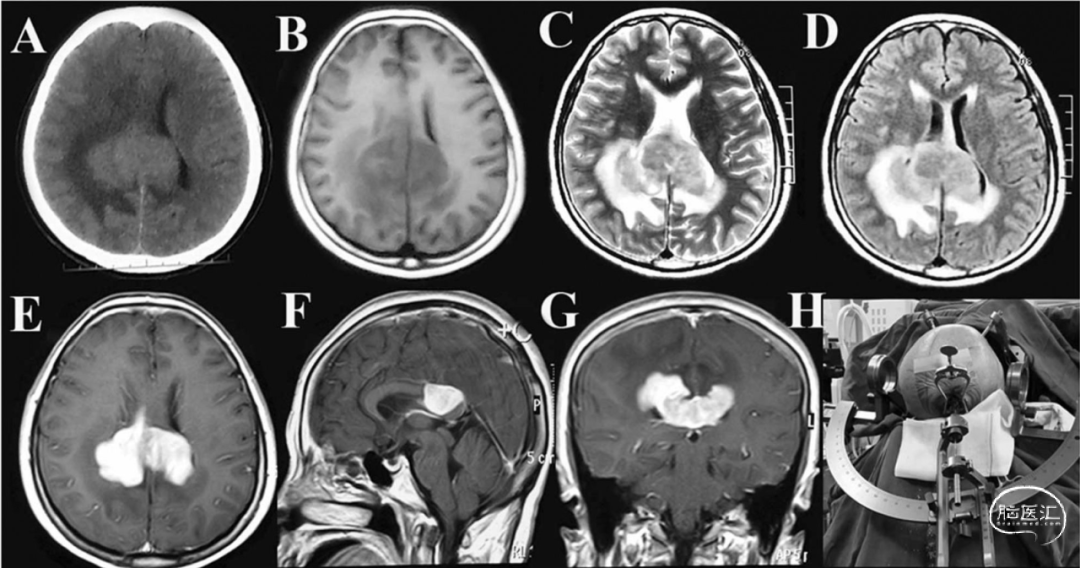

首选检查是增强MRI,如果肿瘤长在脑组织里,通常会表现为不规则、均匀增强、弥散受限的病灶,就像个在大脑里“发光的异物”。

这家伙的影像学表现和很多其他脑部疾病撞脸,比如胶质母细胞瘤、脑转移瘤、脑梗死、脱髓鞘疾病、炎症甚至感染。所以,单凭影像不能武断下结论,一定要靠病理检查确认!